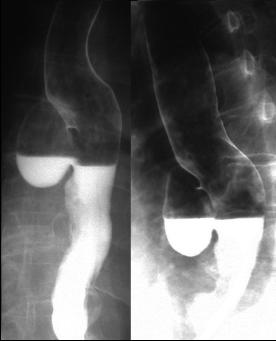

Image TOGD d'une megaoesophage sur

le cliche de face et OAD . Bord lisse et

aperistaltisme ., la retressisement a inferieure est

image en queue de radis |

Megaoesophage en face

et en profile OAD |